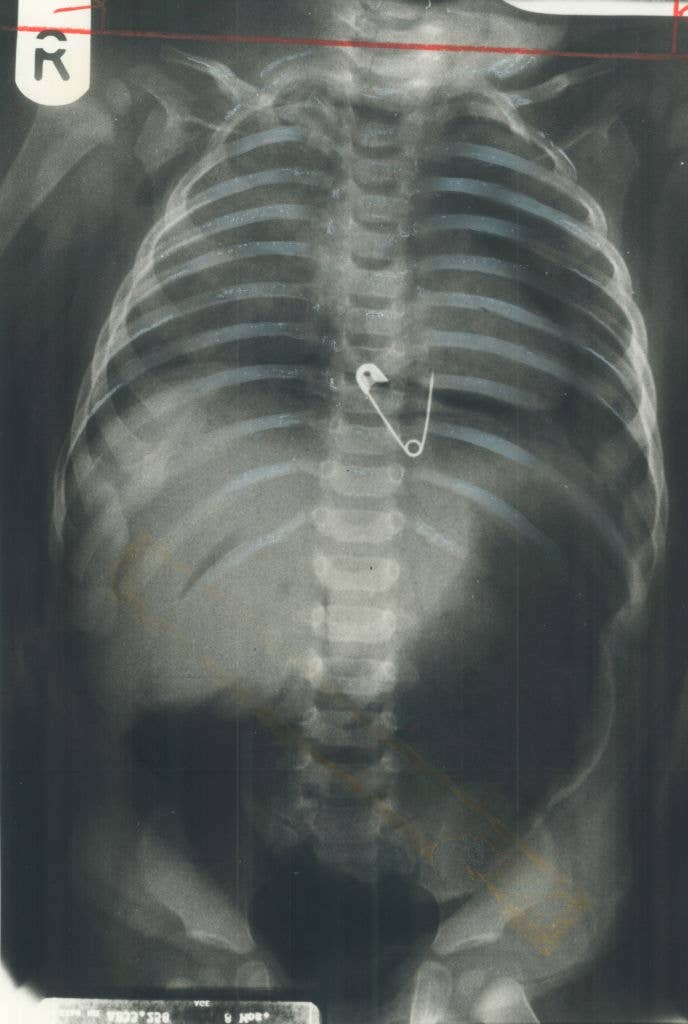

Be honest, is it actually wilder than Grey’s Anatomy? 👀